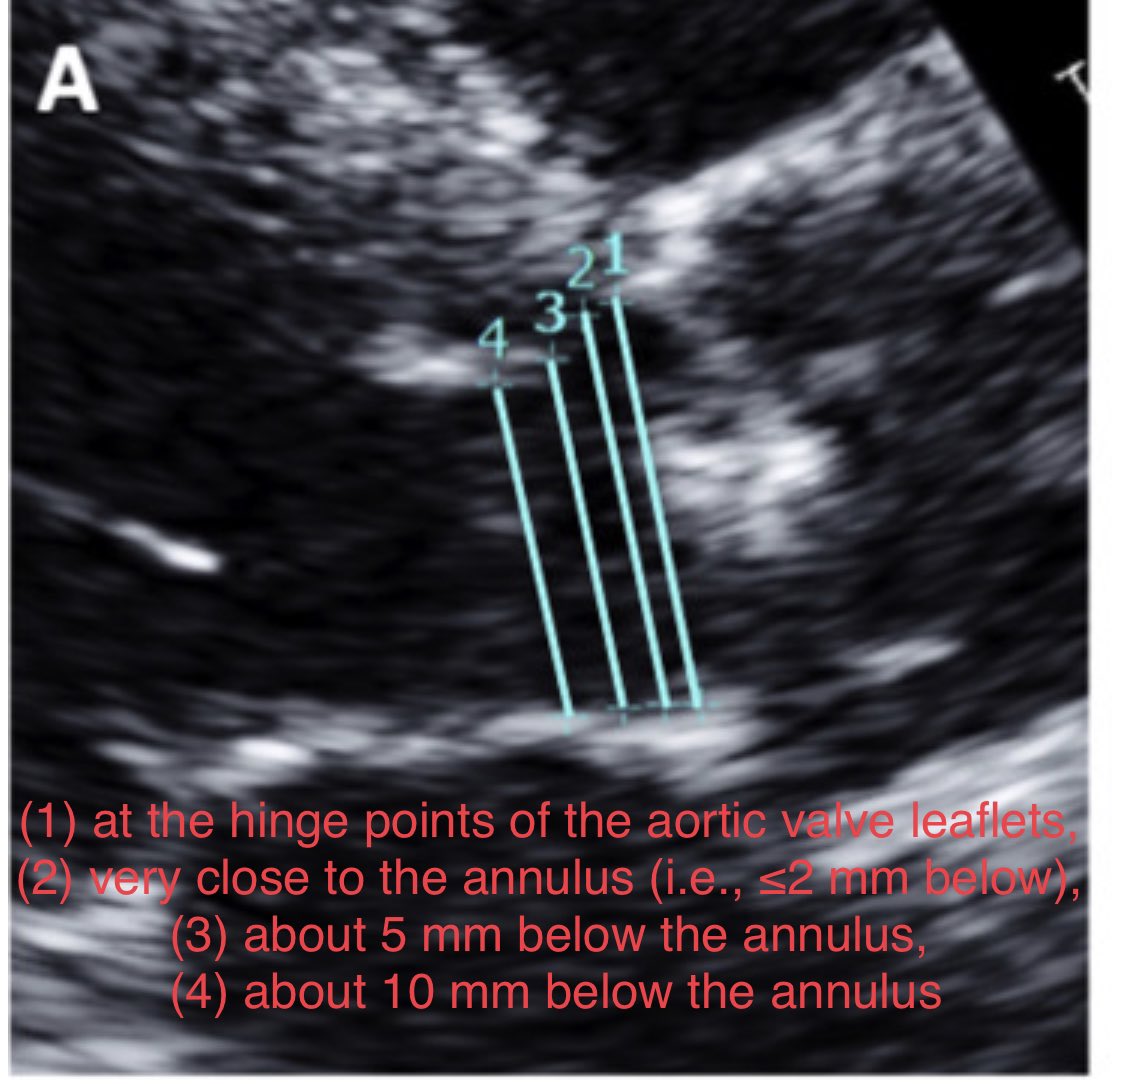

https://t.co/NOgGkU0QVv For aortic stenosis 🔺measure LVOT diameter 5-10 mm below annulus?? 🔺this UNDERestimates SV/AVA & OVERestimates AS severity & low flow status 🆚 #WhyCMR 🔺Measure LVOT diameter at annulus: agrees best with #WhyCMR SV & AVA #echofirst @JournalASEcho